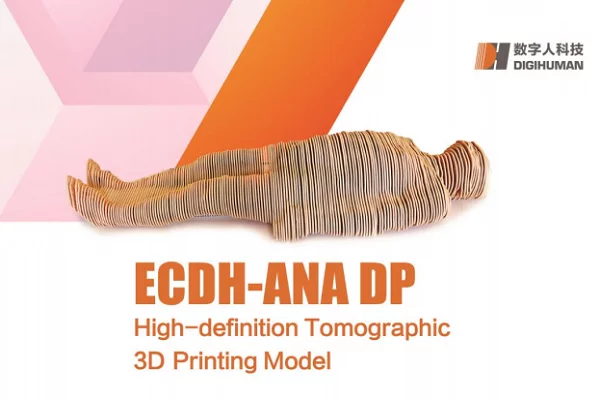

Human Anatomical Model Nowadays with the development of internet, we’ve got decided to reach a broader audience. We expect to provide human anatomical model

Anatomical Brain Model We are eager to cooperate with foreign companies which care much on the real quality, competitive prices, feliable capacity and first-rate